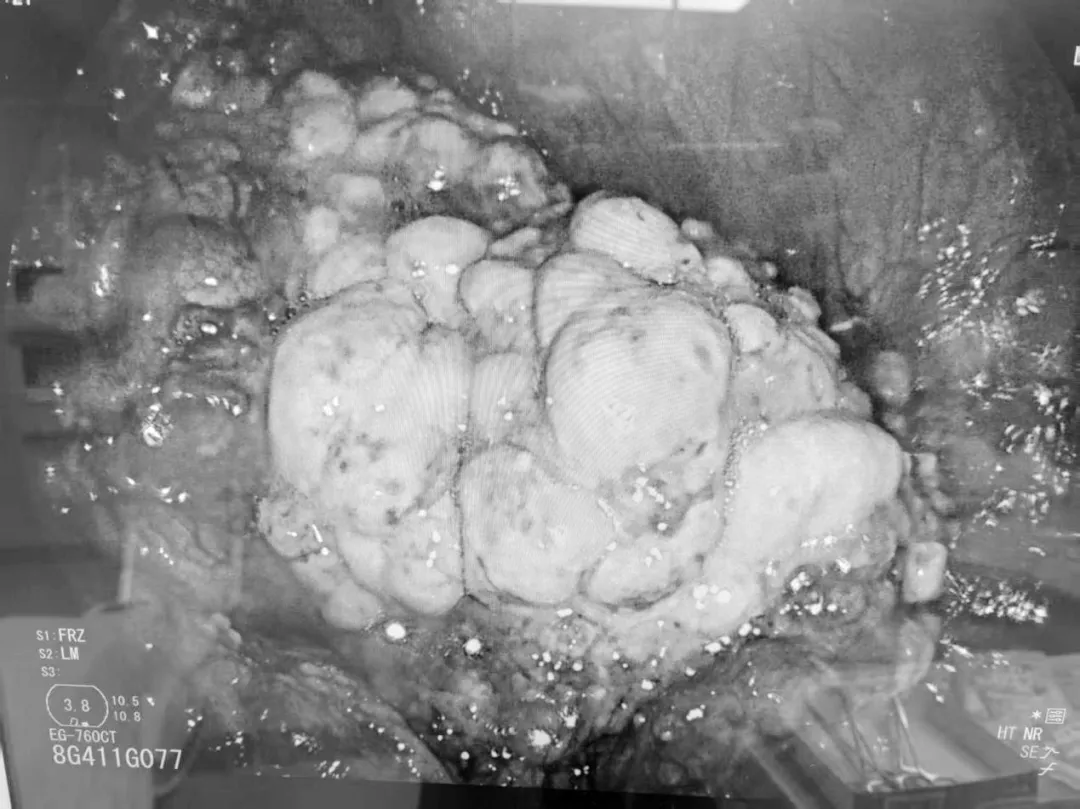

手术中,专家团队通过患者脐部这一天然褶皱处建立微小通道,将胃镜灵活引入腹腔。在清晰的內镜视野下,团队对腹腔进行了系统、全面的探查。最终,在腹腔内发现了腹膜病灶,并成功实施了精准活检。术后病理回报确诊为“高级别浆液性癌”。这一关键诊断,一举揭开了肿瘤来源的迷雾,为后续精准治疗指明方向。